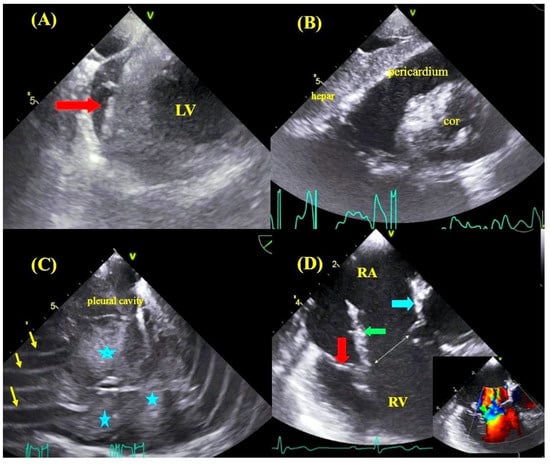

2.3. Transesophageal Echocardiographic Monitoring